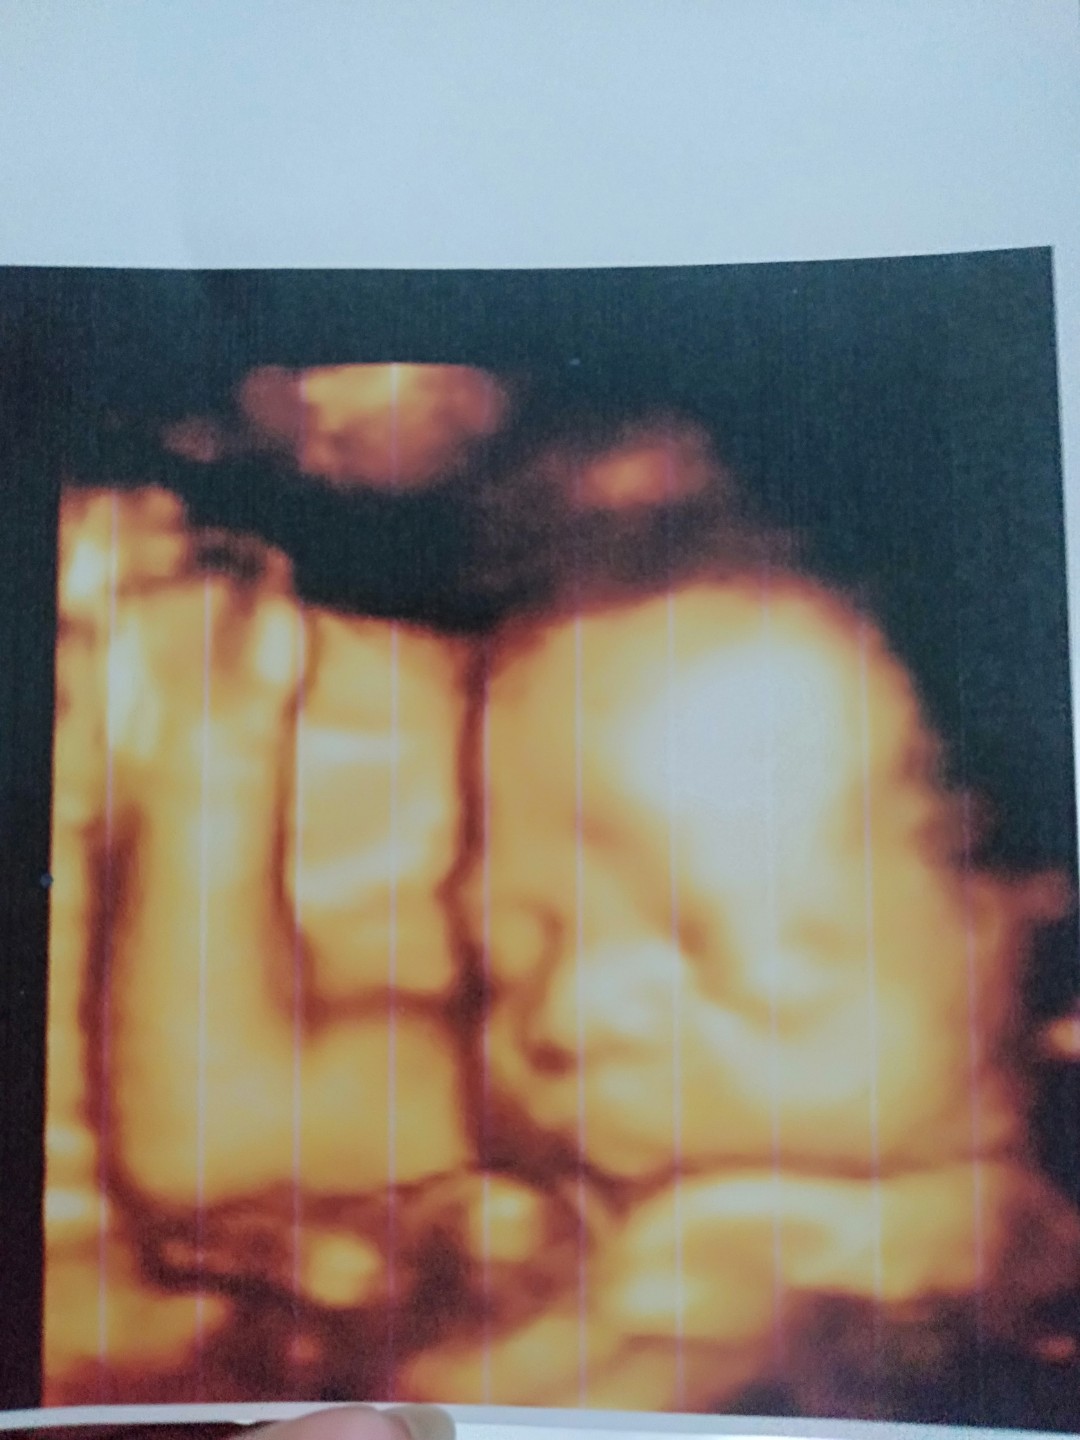

Ini waktu 32 Minggu ... Mukanya cemberut ๐คญ๐ค skrg dah 35 Minggu .. dah ga sabar ketemu buah hatiku ๐